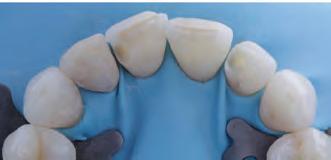

Dental matrix systems: Several commercially available stock matrices are available to the dentist (e.g. Bioclear, Unica and others) to facilitate the placement of composite resins. These matrices (Fig. 3) are appropriate for almost any size and type of restoration.28 They are inserted under dental dam isolation and positioned between the rubber dam and the tooth.29 The rubber dam acts as a rubber band around the tooth, sealing it against the tooth, thus preventing excess material from penetrating the sulcus and creating ledges.28 Additionally, since the composite is polymerized against a very smooth surface, minimal or non-finishing is typically required in the proximal areas. Leaving this highly smooth surface prevents minimal plaque and calculus accumulation.29

Monochromatic materials are used with these matrices and involve the injection of a flowable (no light-curing) followed by a conventional viscosity that extrudes the flowable. This process aids in the insertion of material and elimination of voids.25 The authors prefer heated composites, which can further help their insertion. If a polychromatic restoration is desired, a cut-back approach (also called the window technique) can be employed, involving the removal of some facial composite and its replacement with other opacities and stains to produce halos and incisal translucency.28 These matrices provide suitable proximal contour, but attention should be paid to plastic matrices that require thickness for stiffness, potentially resulting in open contacts. The facial

and lingual surfaces still need contouring and polishing to replicate anatomical contours and blending, which can be considered a disadvantage of this method.

The Bioclear matrices deserve special attention since they are presented as an excellent alternative for closing black triangles and closing diastemas. These matrices prevent any gingival excess in the interproximal area, which is difficult to access for removal and finishing, but instead extrude any excess onto the facial or lingual, where contouring and polishing are more accessible.28 The instruments required for this technique are the same as the free-hand technique with the addition of the matrices.25 When used for black triangles and diastema closures, the clinician can establish the optimal curvature for closing gingival embrasures.29 The Bioclear black triangle kit comes with a colour-coded gauge inserted into the black triangle or diastema space and then corresponding with colours at the top of the matrix.28 This allows the clinician to choose the appropriate size and contour matrix.28,29 In the author’s experience, selecting one size larger matrix than the corresponding colour from the colour-coded gauge is better. The matrices are offered in two sizes (big and small) and four curvatures (red, yellow, green, blue), allowing the operator to treat the entire anterior sextant, from canine to canine, in both upper and lower arches.28 This results in robust and esthetically acceptable outcomes.29 Patients with substantial midline diastemas often lack interdental papilla, influenced by the distance between the interdental contact point and the alveolar bone crest.29,30